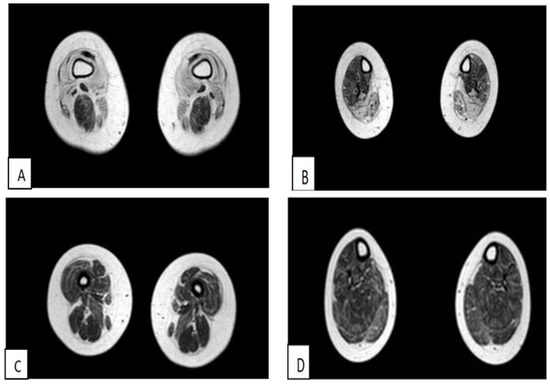

3.1.1. The First Case of Family 1 (Patient 1)

3.1.2. Second Case of Family 1 (Patient 2)

3.1.3. First Clinical Case of Family 2 (Patient 3)

3.1.4. Second Case of Family 2 (Patient 4)

3.1.5. Third Case of Italo-Spanish Family (Patient 5)

3.1.6. Fourth Case of Italo-Spanish Family (Patient 6)